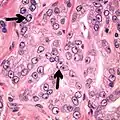

Acinar adenocarcinoma with multiple nucleoli.

Acinar adenocarcinoma with double and eccentric nucleoli.